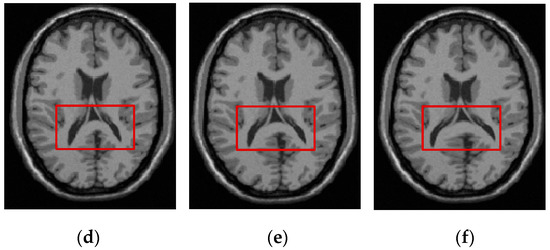

Figure 10 shows the registration results of 3D CT-MR images for all the evaluated methods. As shown in Figure 10c,d, the ESSD and MIND method cannot effectively correct the deformation that is involved in the MR image. The FMIND method can produce a more similar registration result to the reference image that is shown in Figure 10a than the ESSD and MIND methods. When compared with the most competitive HLCSO method, the proposed method performs better in that it can correct the deformation of some tissues more effectively, as indicated by the three red boxes that are shown in Figure 10e,f.

Figure 10.

The registration results of all evaluated methods operating on 3D CT–MR images. (a) CT image (reference image); (b) MR image (float image); (c) ESSD; (d) MIND; (e) HLCSO; and, (f) FMIND.